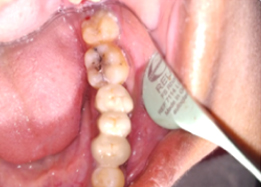

Hemisectomy

Placement of PRF Membrane